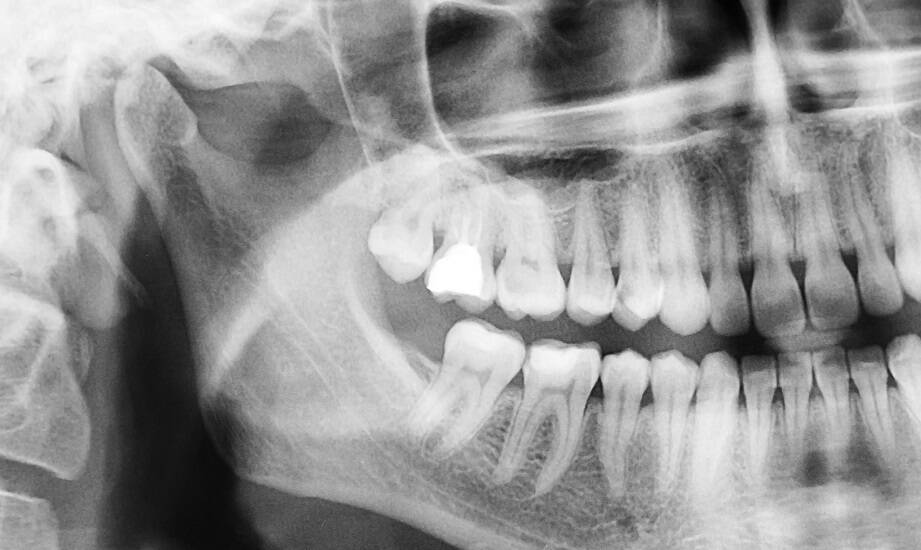

Technologia rentgenowska znajduje zastosowanie w różnych dziedzinach stomatologii, takich jak chirurgia, endodoncja w Krakowie czy protetyka. W każdej z tych specjalizacji precyzyjne obrazy są niezbędne do podejmowania właściwych decyzji dotyczących leczenia pacjentów. W endodoncji, znanej także jako leczenie kanałowe, dokładne zdjęcia rentgenowskie umożliwiają precyzyjne zlokalizowanie zmian chorobowych oraz ocenę stanu tkanek okołowierzchołkowych. Dzięki temu dentyści mogą skuteczniej przeprowadzać zabiegi i minimalizować ryzyko powikłań.

W chirurgii stomatologicznej obrazy te wspierają planowanie skomplikowanych operacji, takich jak usunięcie ósemek czy rekonstrukcje kości szczękowej. Natomiast w protetyce umożliwiają dokładne odwzorowanie kształtu i funkcji utraconych zębów, co przekłada się na lepsze dopasowanie protez oraz większy komfort dla pacjentów. Nowoczesne urządzenia do zdjęć panoramicznych i punktowych znajdujące się w laboratorium rentgenowskim gwarantują wysoką jakość obrazów przy minimalnej dawce promieniowania.